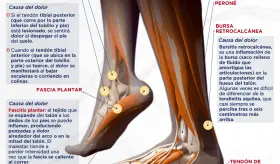

#InfografíaMSP El uso frecuente de tacones altos altera la postura, sobrecarga el antepié y afecta desde los pies hasta la columna vertebral, aumentando el riesgo de juanetes, dolor muscular y desgaste articular.